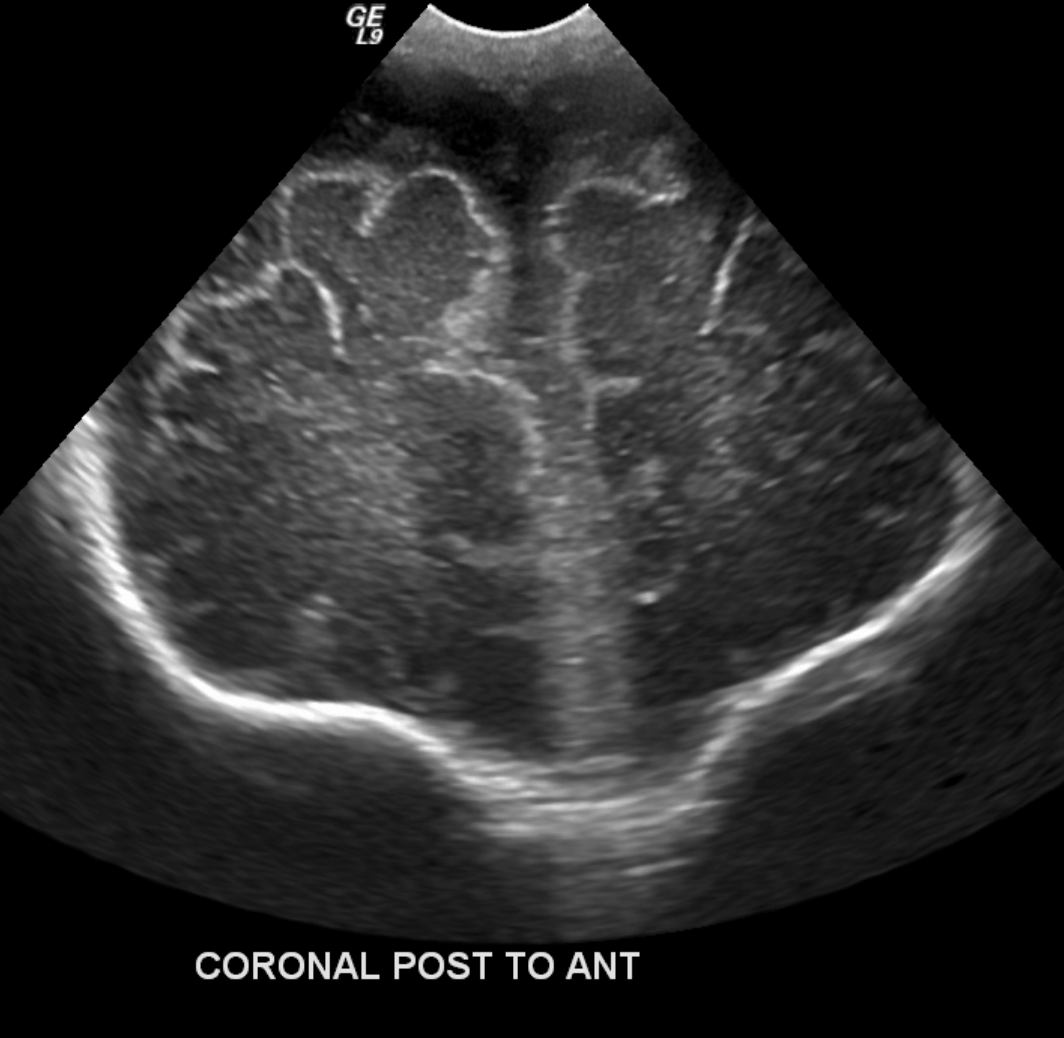

Info Images Findings Impression Reco/Acuity Case Images View Images / Launch Visage Case Notes History Full term infant. We are asked to evaluate posterior fossa cyst. Exam Gray scale and Doppler Ultrasonographic examination of the head. Prior Study N/A Dicom View Reference Material

Section 1 Submit Findings Case149 Findings Brain The brain is immature. Yes No There is under-sulcation and open sylvian fissures. Yes No There is/are multiple hypoechoic areas in the periventricular white matter. Yes No There is/are multiple hyperechoic areas in the periventricular white matter. Yes No There is diffuse cerebral edema with diffusely increased echogenicity of the brain parenchyma and loss of grey white matter differentiation. Yes No The thalami/basal ganglia are hypoechoic. Yes No There is periventricular calcification. Yes No There is intra-parenchymal calcification. Yes No CSF spaces/ventricular system There is a prominence of the extra axial fluid spaces. Yes No There are debris/septations in the extra axial fluid spaces. Yes No There are debris/septations in the ventricles. Yes No There is a subdural collection on the right/left side. Yes No There is prominence of the ventricular system. Yes No There is an asymmetry of the ventricular system. Yes No There is a cavum septum pellucidum. Yes No There is a midline shift towards right/left. Yes No The choroid plexus is bulky/lobulated. Yes No There is a choroid plexus cyst measuring… Yes No There are debris/clots in the occipital horn. Yes No There is a posterior fossa cyst measuring… Yes No The tentorium is elevated/depressed. Yes No The lateral ventricle/s are dilated. Yes No The third ventricle is dilated. Yes No The 4th ventricle is dilated. Yes No There are pseudo cysts. Yes No Germinal matrix hemorrhage (Only in the premature infants): Please do not answer if the patient is a full term. There is a germinal matrix hemorrhage, consistent with a grade I hemorrhage. Yes No There is an intraventricular extension consistent with a grade II hemorrhage. Yes No There is an intraventricular extension with the dilatation of ventricles, consistent with a grade III hemorrhage. Yes No There is an intra-parenchymal extension, consistent with grade IV hemorrhage. Yes No On color Doppler examination, the Resistive index in the anterior cerebral artery is… There is a loss of the diastolic flow on the Doppler exam. Yes No There is altered vascularity on Doppler imaging. Yes No There is an AVM in the region of… Yes No